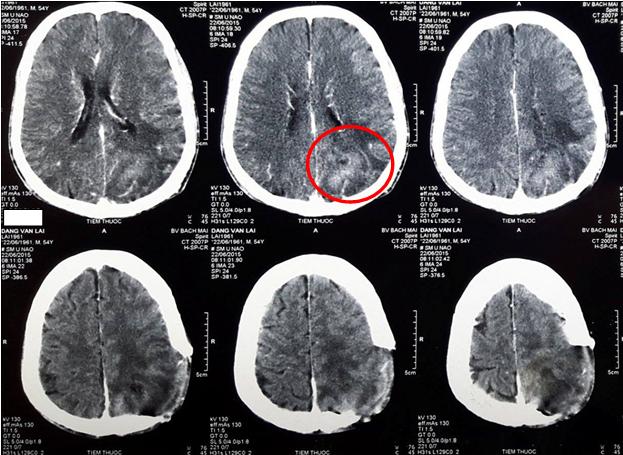

Hình ảnh phim chụp cộng hưởng từ sọ não trước mổ cho thấy khối u não vị trí thùy đỉnh - chẩm bên trái, kích thước 45 x 56mm, ngấm thuốc mạnh, phù não rộng xung quanh.

Hình 1: Hình ảnh u não thùy đỉnh - chẩm trái (vòng tròn đỏ)

Sau phẫu thuật lấy u não, bệnh nhân được chụp cộng hưởng từ sọ não đánh giá lại sau mổ, kết quả cho thấy vùng khuyết não vị trí đỉnh chẩm trái, còn tổ chức u ngấm thuốc và vùng phù não rộng xung quanh.

Hình 2: Hình ảnh còn tổ chức u sau mổ và vùng phù não xung quanh (vòng tròn đỏ)

Chụp phim cộng hưởng từ sọ não đánh giá sau quá trình điều trị cho thấy khối u thu nhỏ kích thước: 1x2 cm, còn phù não nhẹ xung quanh.

Hình 3: khối u kích thước nhỏ còn lại sau điều trị (vòng tròn đỏ)